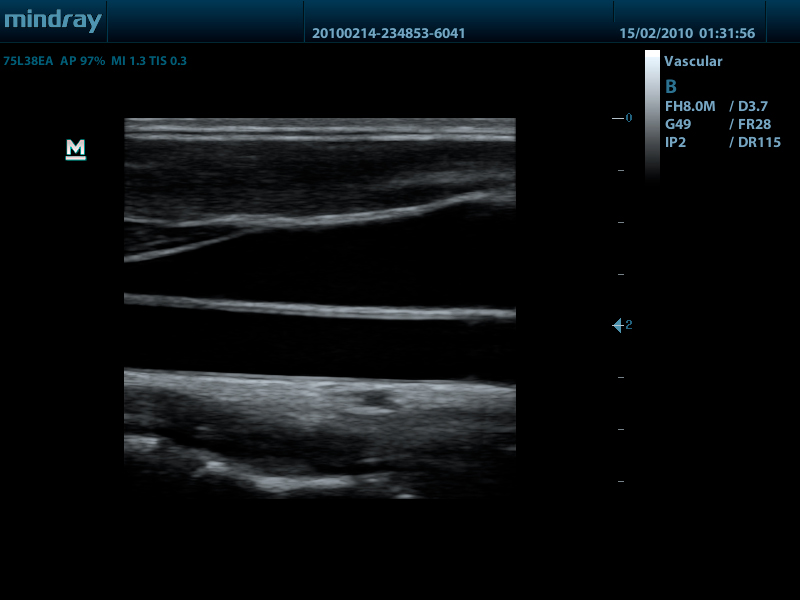

- Линейный датчик 75L38EA, 3.3 - 13.0 МГц, апертура 38 мм